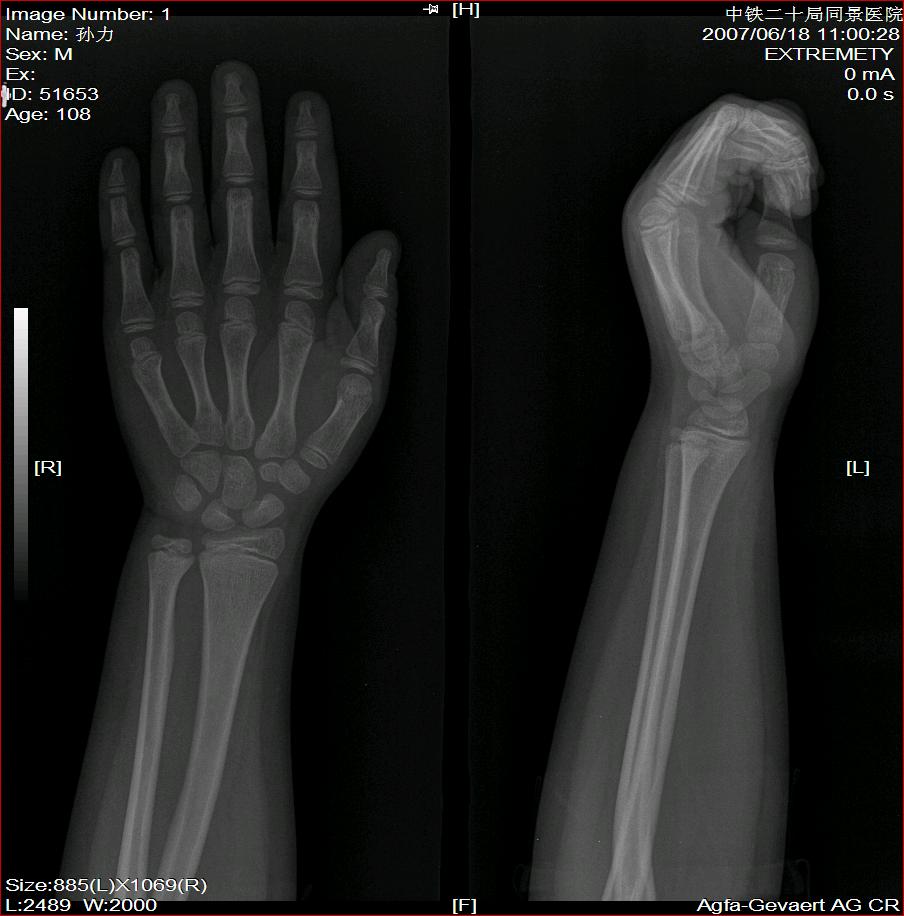

标题: X2504:M17Y,高中生,身高不足1.2米,智力正常 [打印本页]

年龄17岁,身材矮小(1.2m),全身骨骼发育迟缓,骨骺线仍较宽,但全身骨骼骨质正常,智力正常。

骨结构正常,骨骺线与17岁不符,豆状骨未见,相当7-8岁骨龄,结合智力正常,垂体性侏儒可能大。

考虑垂体侏儒的可能。依据1骨龄延迟,骨胳结构正常,智力正常。与甲状腺功能不足区别呆小症病人长骨及骨垢有改变,骨垢较正常小。椎体变扁。考虑垂体侏儒症。

骨结构正常,骨骺线与17岁不符,豆状骨未见,相当7-8岁骨龄,结合智力正常,支持垂体性侏儒症。

各部比例在正常范围,为均称型侏儒,可见于1、垂体性侏儒。2、致密性骨发育不全。3、turner氏综合症。本例骨密度正常,皮质边界清,显然不支持致密性骨发育不全,未见掌骨征阳性和指骨优势,turner氏综合症,可基本除外,剩下的只有垂体性侏儒了,建议垂体mri进一步检查,确定诊断。以上主要参考曹来宾教授发表的论文,侏儒症的临床x线分析

全身骨骼发育迟缓,骨骺线仍较宽与年龄不符。考虑垂体性侏儒可能大。